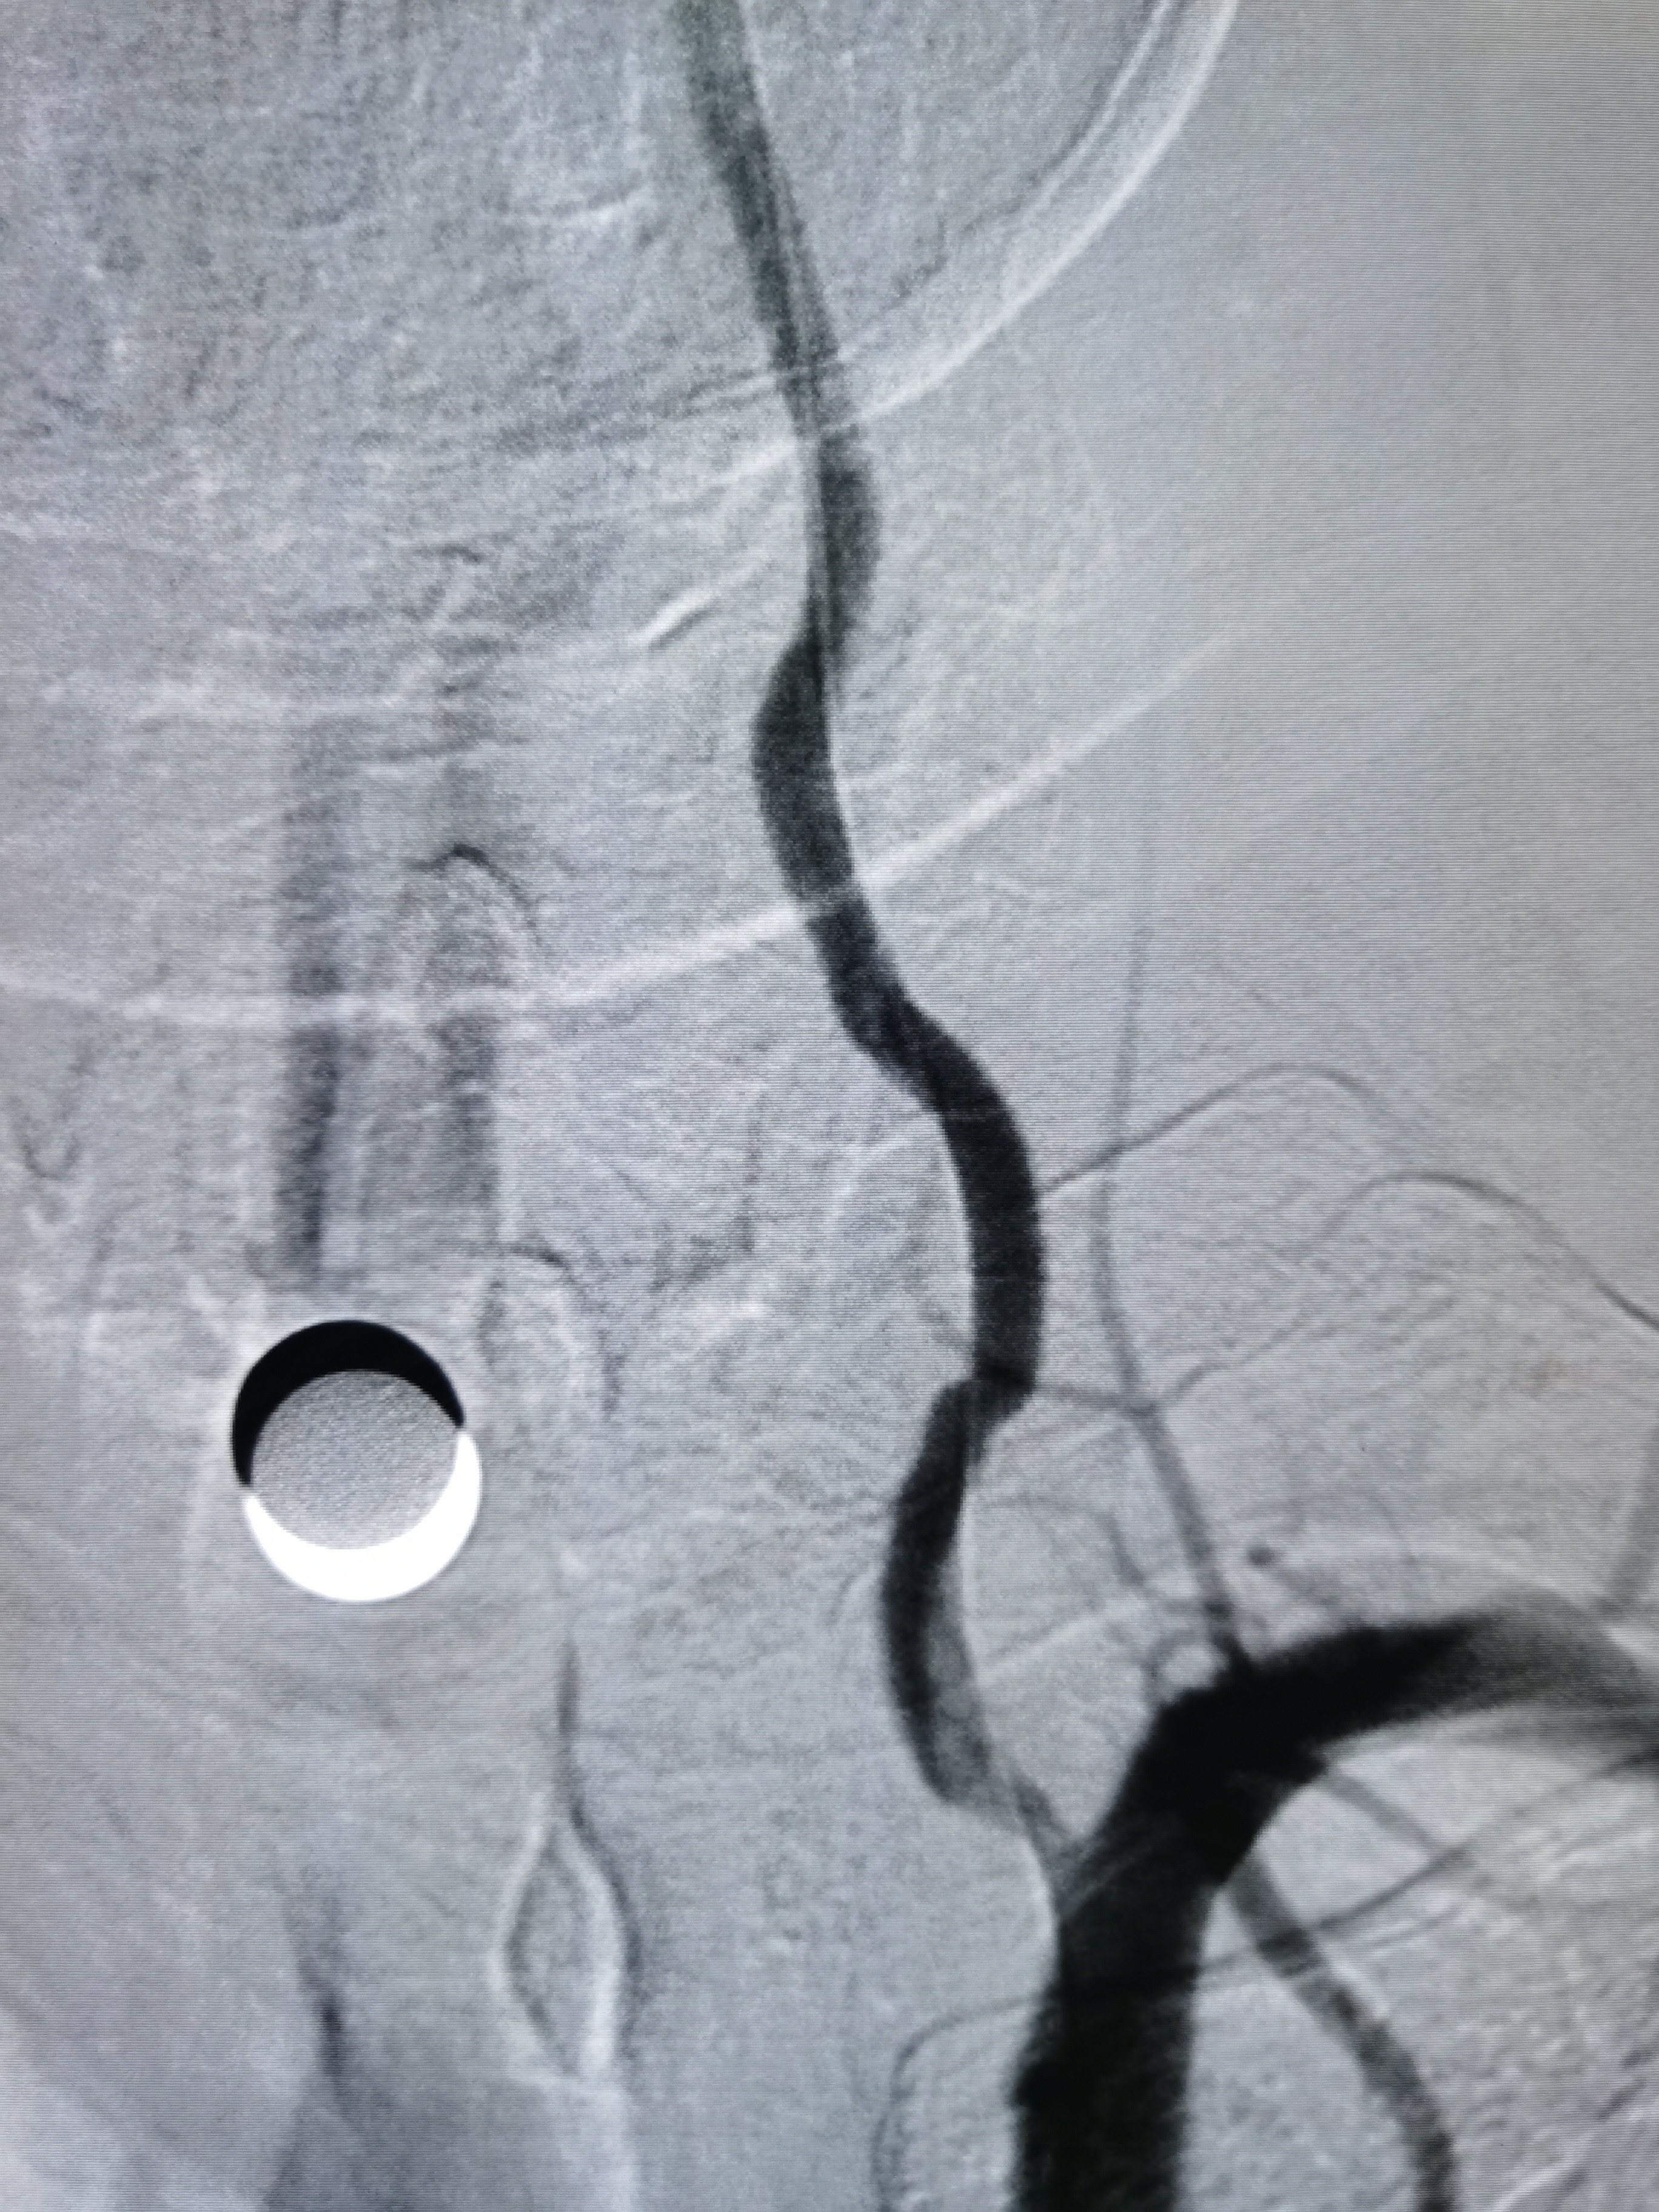

将8F导引导管送至左侧锁骨下动脉近左椎动脉起始部,微导丝顺利通过病变,2.0/20球囊预扩病变。

3、手术过程中,先用小球囊扩张病变,观察血栓情况,及时应用支架全程覆盖血栓及病变部位,成形满意。